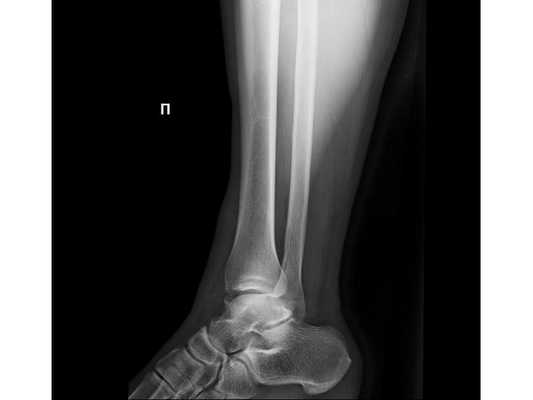

При осмотре определяется отёк мягких тканей области голеностопного сустава. Геометрия сустава изменена. Движения в голеностопном суставе ограничены болями, при пальпации пациент отмечает боли в этой области. Также при пальпации есть болезненность в верхней трети правой голени в проекции головки малоберцовой кости.

- Рентгенография правого голеностопного сустава в двух проекциях.

- Рентгенография голеностопных суставов в проекции Mortis.

- Рентгенография правой голени на протяжении с захватом коленного и голеностопного суставов.

Закрытый оскольчатый перелом внутренней лодыжки правой голени со смещением отломков. Закрытый перелом верхней трети малоберцовой кости правой голени. Повреждение дистального межберцового синдесмоза ( соединения большеберцовой и малоберцовой костей) . Подвывих стопы кнаружи (Maisonneuve-type fracture).